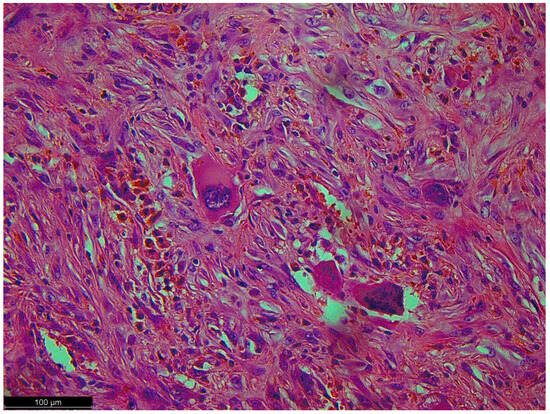

Figure 6.

Pleomorphic cells with high-grade atypia; they did not show typical differentiation. There were no lipoblasts or remnants of well-differentiated liposarcoma (the precursor to this tumor) because a dedifferentiated component had overgrown it.